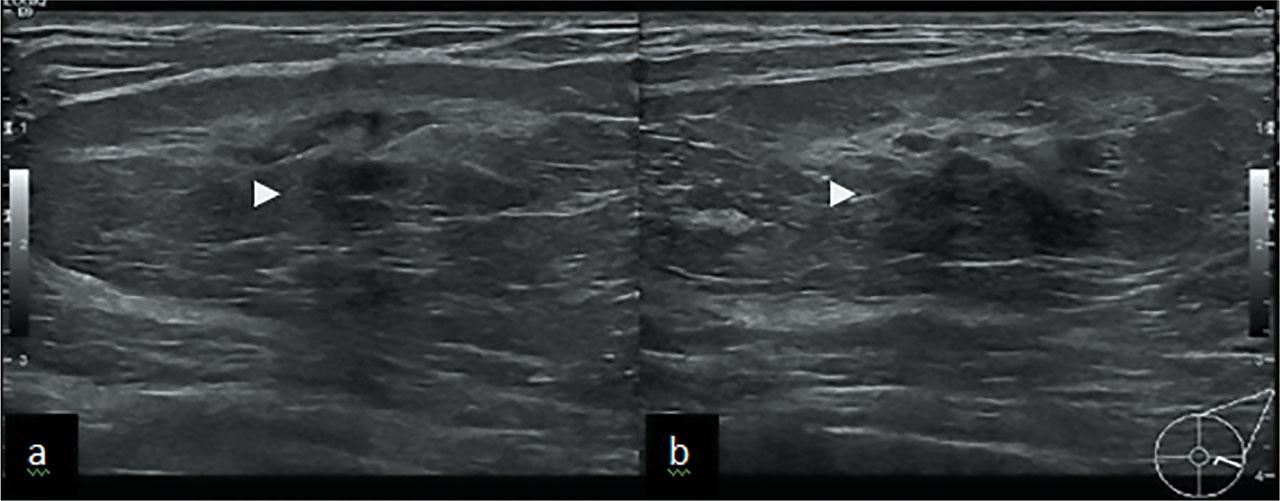

A 61 year old woman was recalled for assessment after a screening mammogram. She was known to have long standing benign lump in her left breast which had shown interval development of central distortion. On clinical palpation, there was mobile mass in left breast. Digital breast tomosynthesis was performed which confirmed the presence of architectural distortion (Figure 3a&b). Ultrasound showed an oval encapsulated mass running parallel to the skin with central hypoechoic areas (Figure 4a&b). The central distortion and corresponding hypoechoic change was suspicious, therefore 14G US guided core biopsy was performed.

US shows well defined oval mass with central hypoechoic shadowing area (arrowheads) corresponding to mammographic distortion.